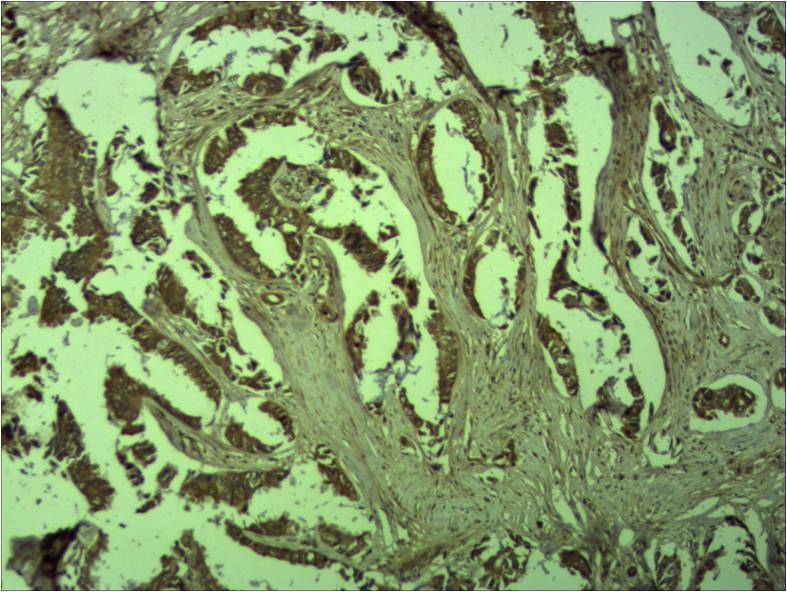

| Dilutions: | WB 1:1,000 IHC 1:500-1,000 |

| Background: | The distinct peripheral cytosolic proteins, alpha, beta and gamma catenin (102, 94 and 86 kDa) are found in many tissues and bind to the conserved cytoplasmic tail domain of the cell adhesion cadherins. Catenins link E cadherin to other integral membrane or cytoplasmic proteins and are modulated by Wnt1 proto oncogene. The central core region of beta catenin is involved in mediation of cadherin catenin complex interaction with EGFR. Beta-Catenin-mediated signalling is involved at several stages of vertebrate neural development. |